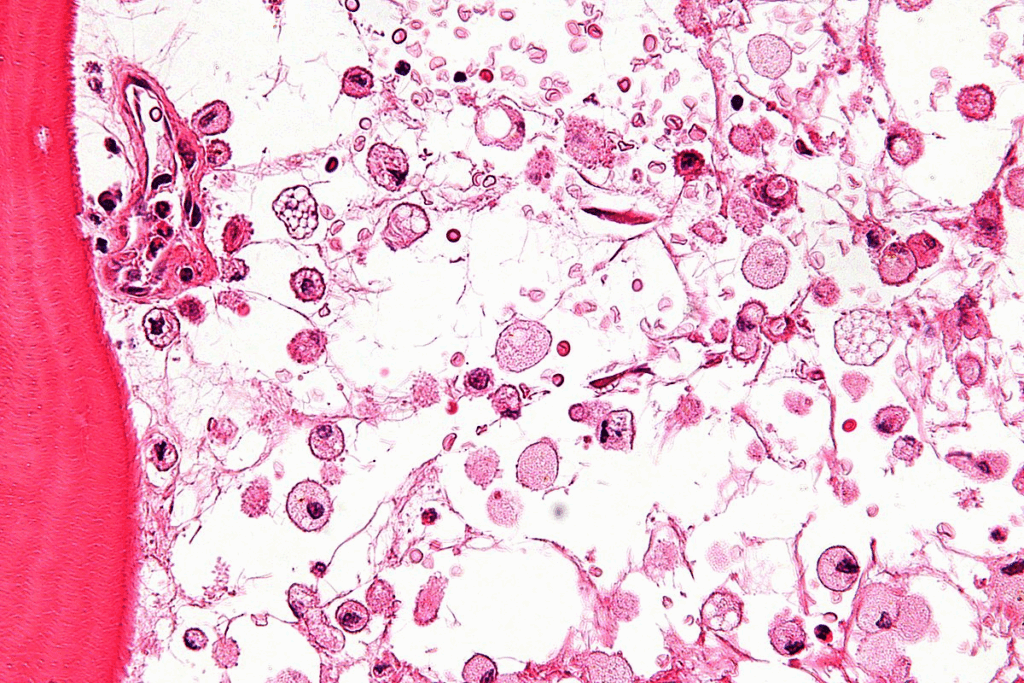

Bone marrow biopsies are medical tests that take a sample of bone marrow for study. They are key to spotting and tracking blood-related issues and diseases.

These tests help us understand how bone marrow works. Doctors look at the marrow to find problems and figure out why blood cell production might be off.

A bone marrow biopsy takes a small piece of bone marrow tissue for a closer look. The main goal is to check the bone marrow’s health and how it works.

Bone marrow aspiration removes a liquid sample from the bone marrow. It’s used to check the marrow’s cells and diagnose blood-related issues. This procedure can spot diseases like leukemia or lymphoma.

A bone marrow core biopsy takes a solid tissue sample. It’s key to looking at the marrow’s structure and finding hidden problems. This biopsy gives a detailed view of the marrow’s health.